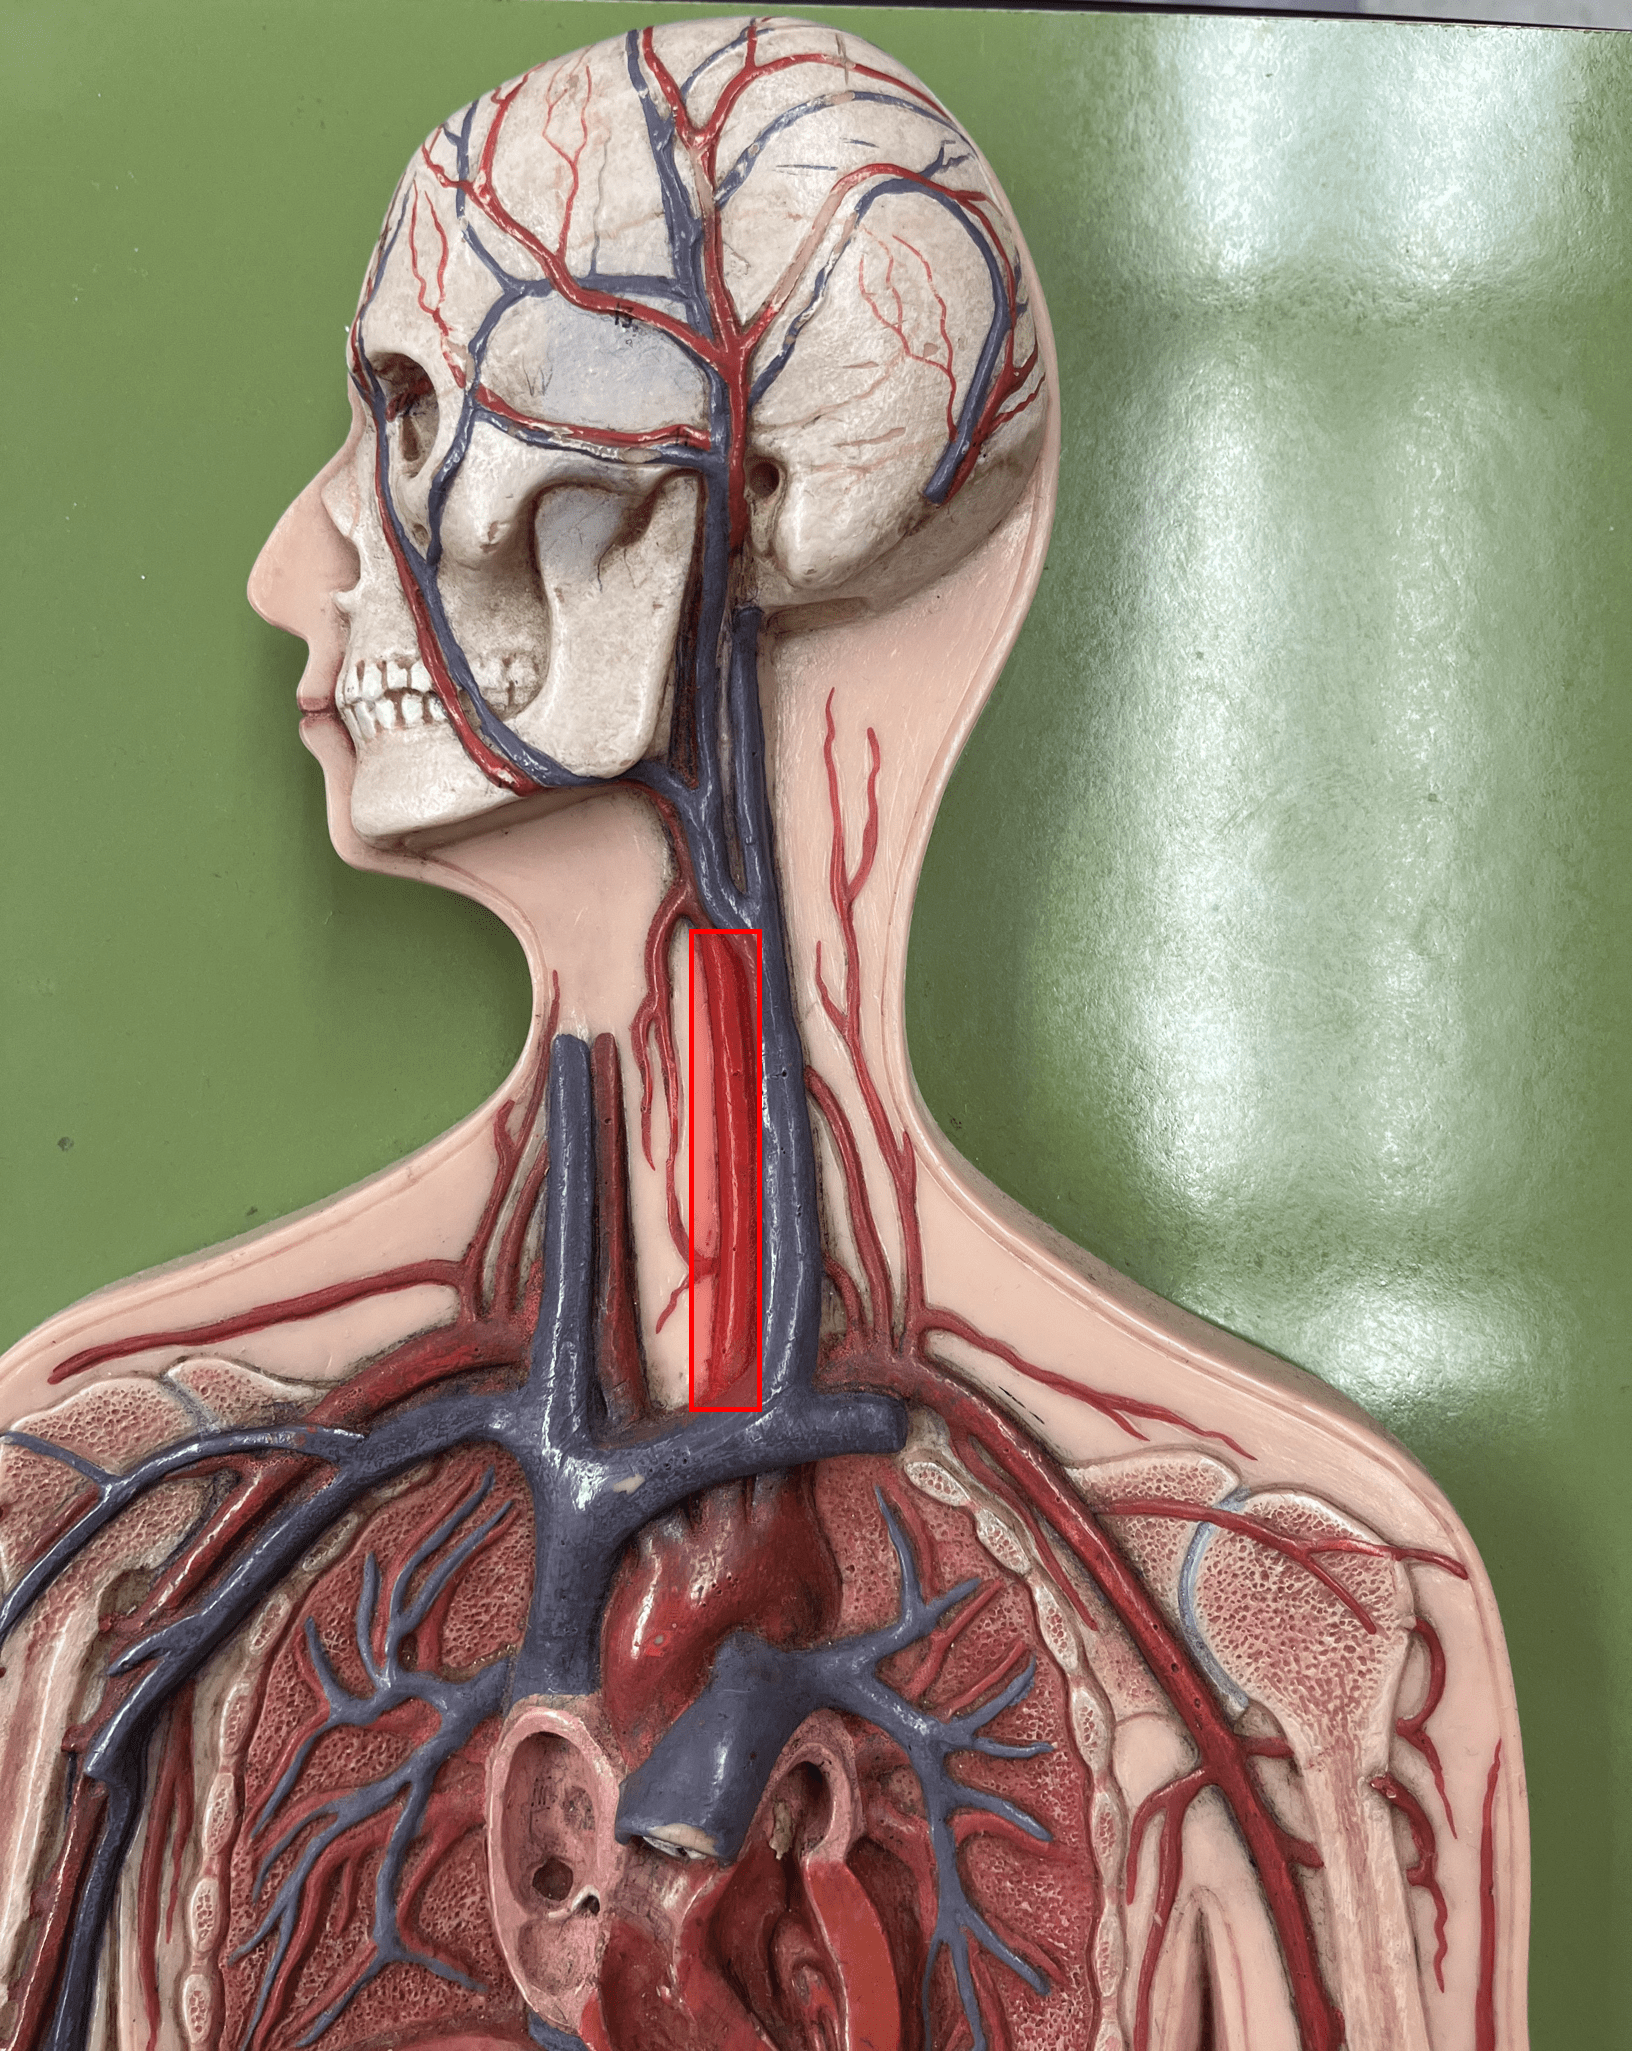

common carotid artery

internal jugular vein

• Drains the brain, face, and neck.

• Empties into the subclavian vein.

• Laterally, the anteriormost vein of the neck.